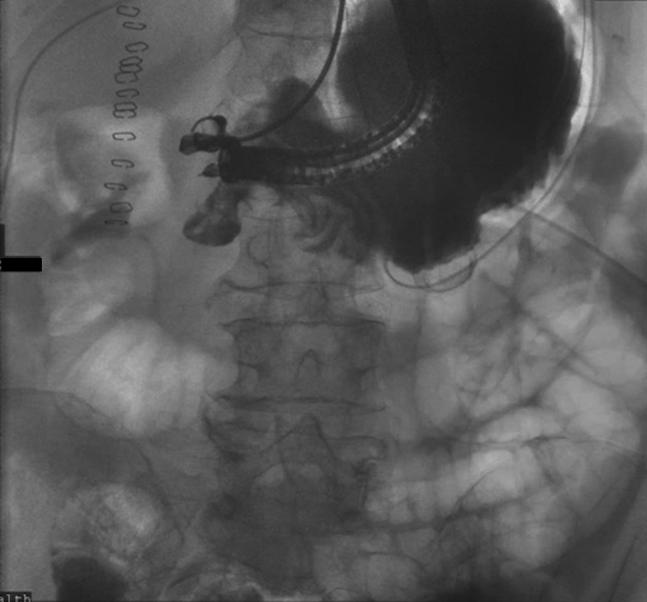

Endoscopic pyloric exclusion-EUS-guided gastrojejunostomy combined with endoscopic suturing and closure of the pylorus: a novel approach to failed surgical repair of a perforated duodenal ulcer.

Video 1Endoscopic pyloric exclusion: same-session EUS-guided gastro-jejunostomy combined with endoscopic suturing and closure of the pylorus.